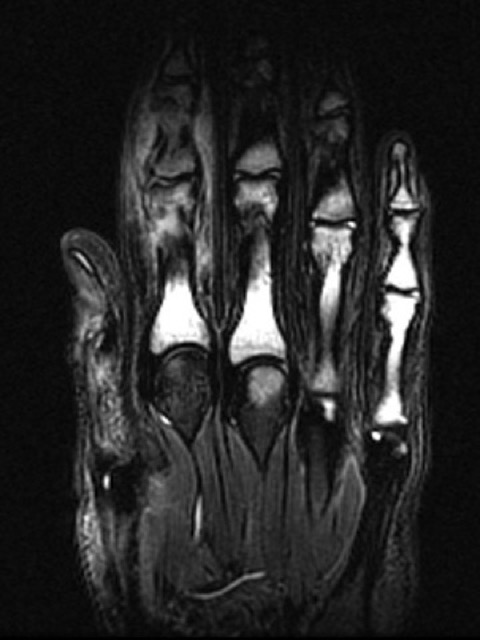

The x-ray findings are localised to the affected phalanx (or phalanges when multiple digits are affected). In contrast, MRI has been reported to show bone marrow oedema in many phalanges of the affected hand, where clinical and radiological findings are absent [5,6].

MRI